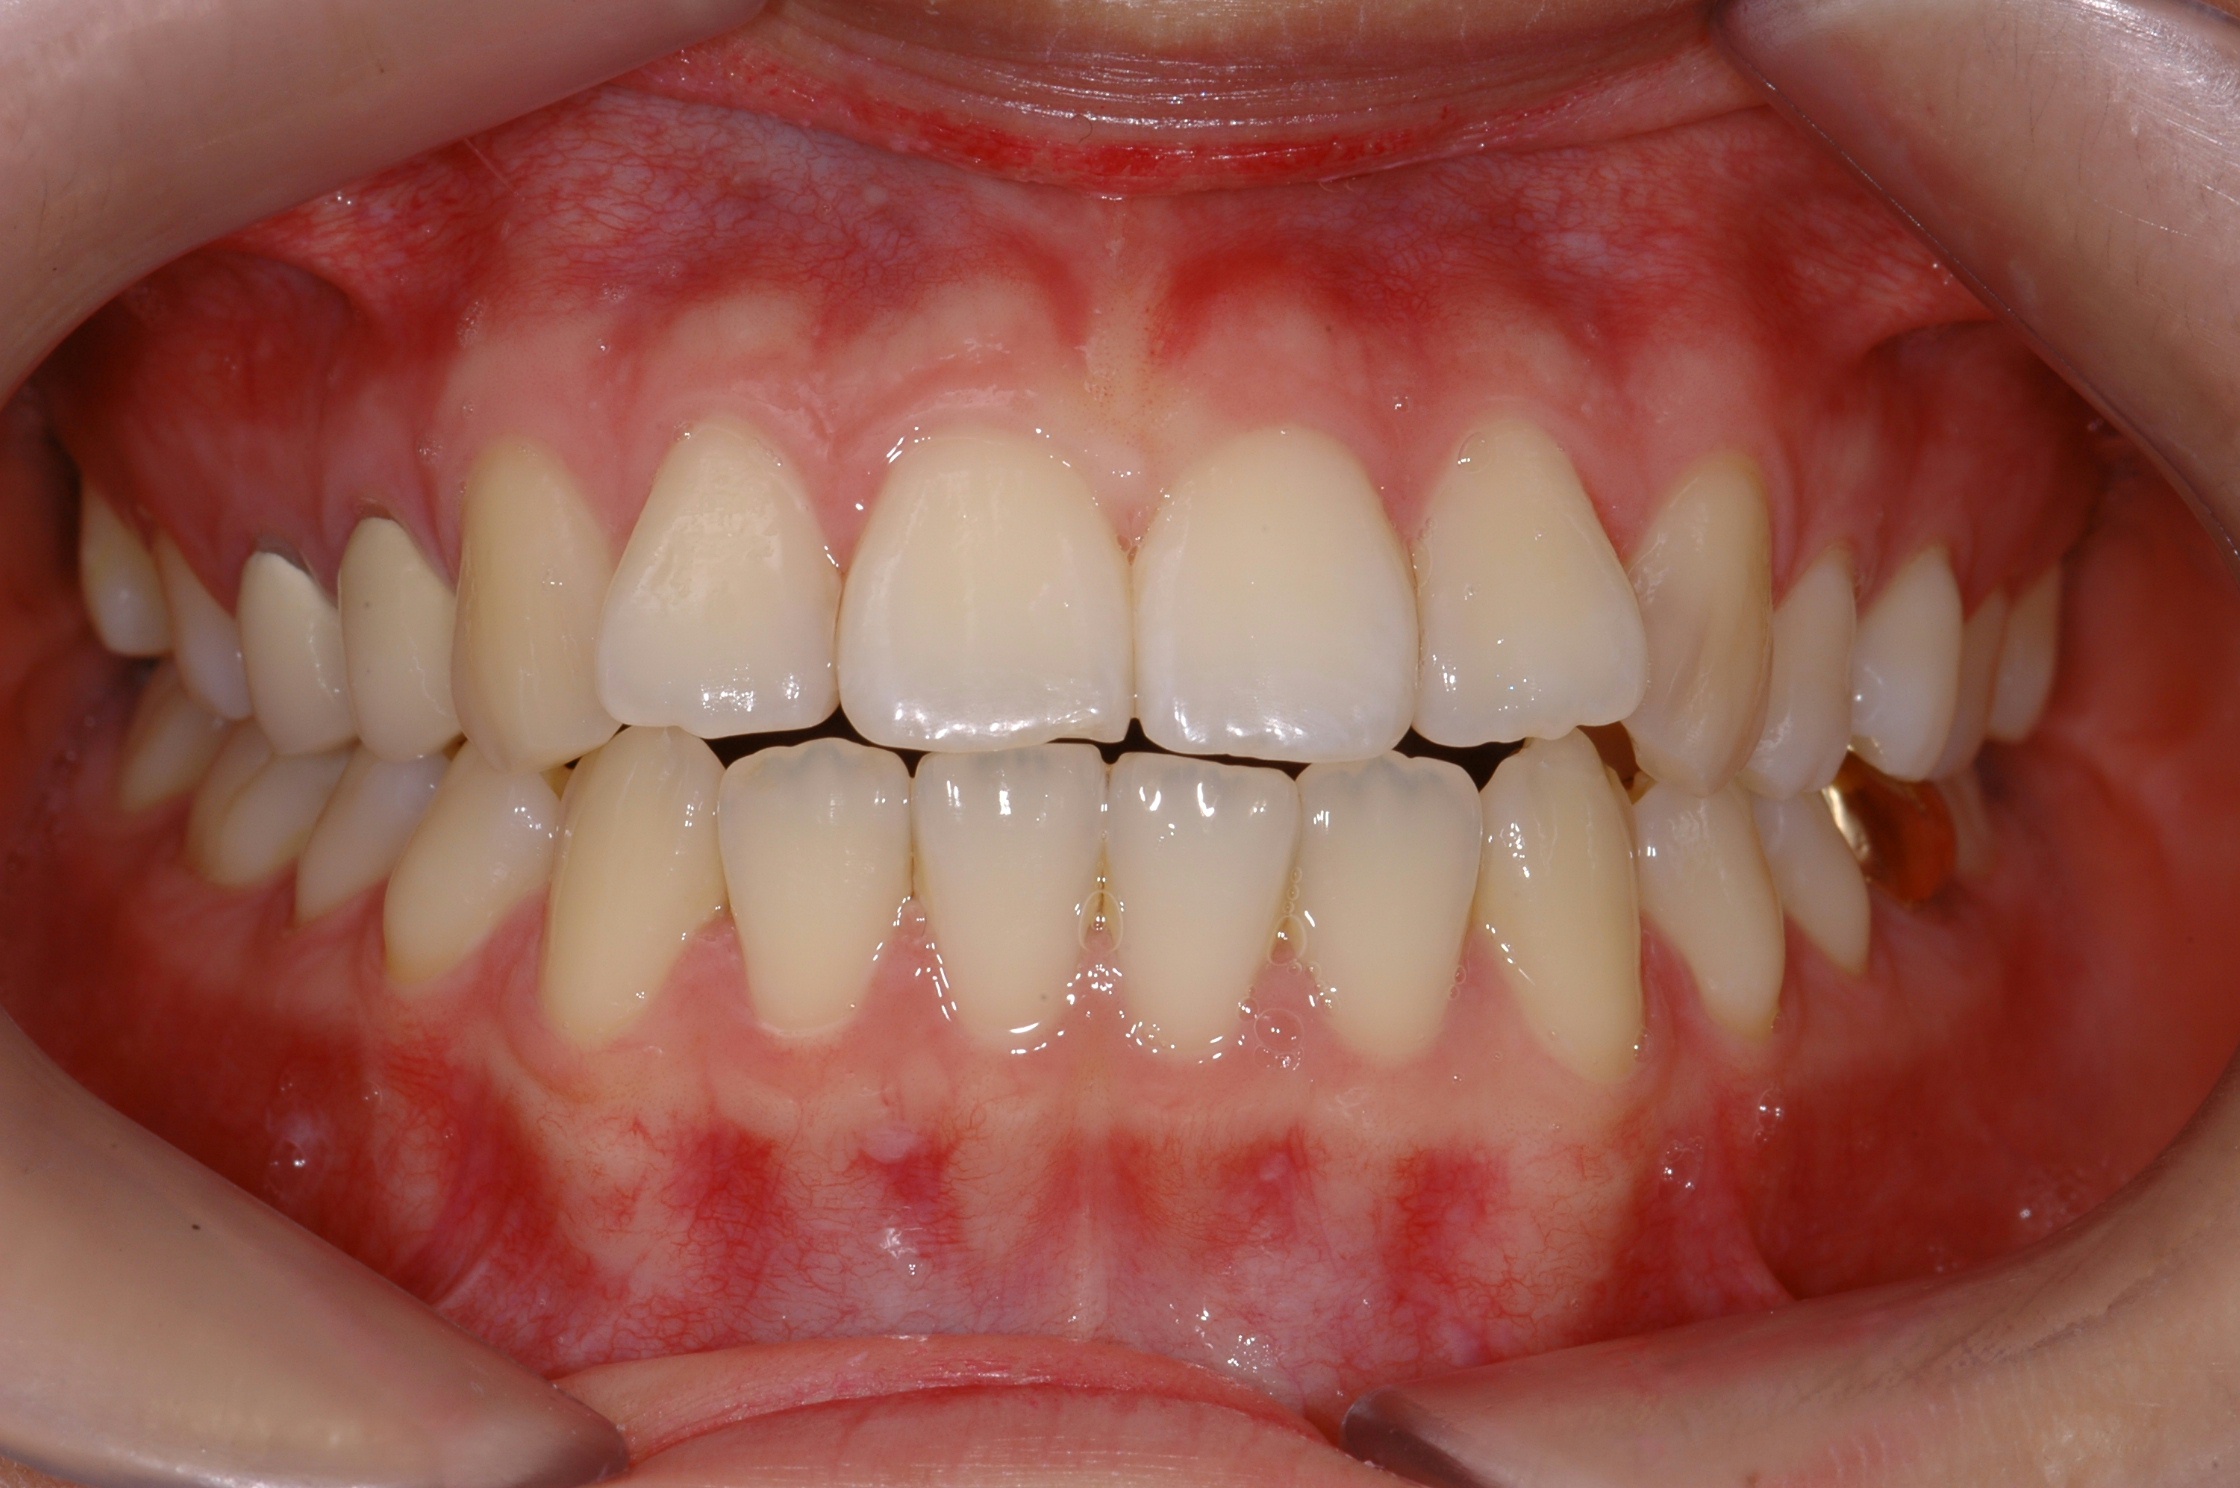

치료 후 사진입니다.